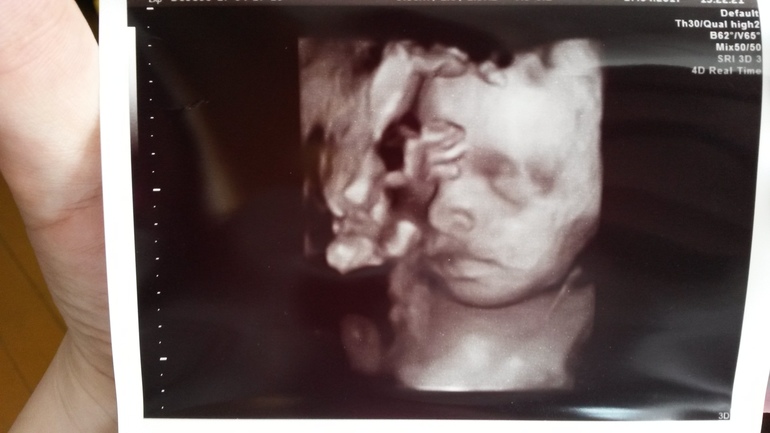

Были моменты когда чуть убирала ото лба ножки)))Тогда и засняли)))Моя радость!Моё солнышко!!!Я сегодня самая счастливая на свете!!!

Ну и наши фото!Доказательство что это Виктория,а не Витя)))

И личико моей красавицы!!!